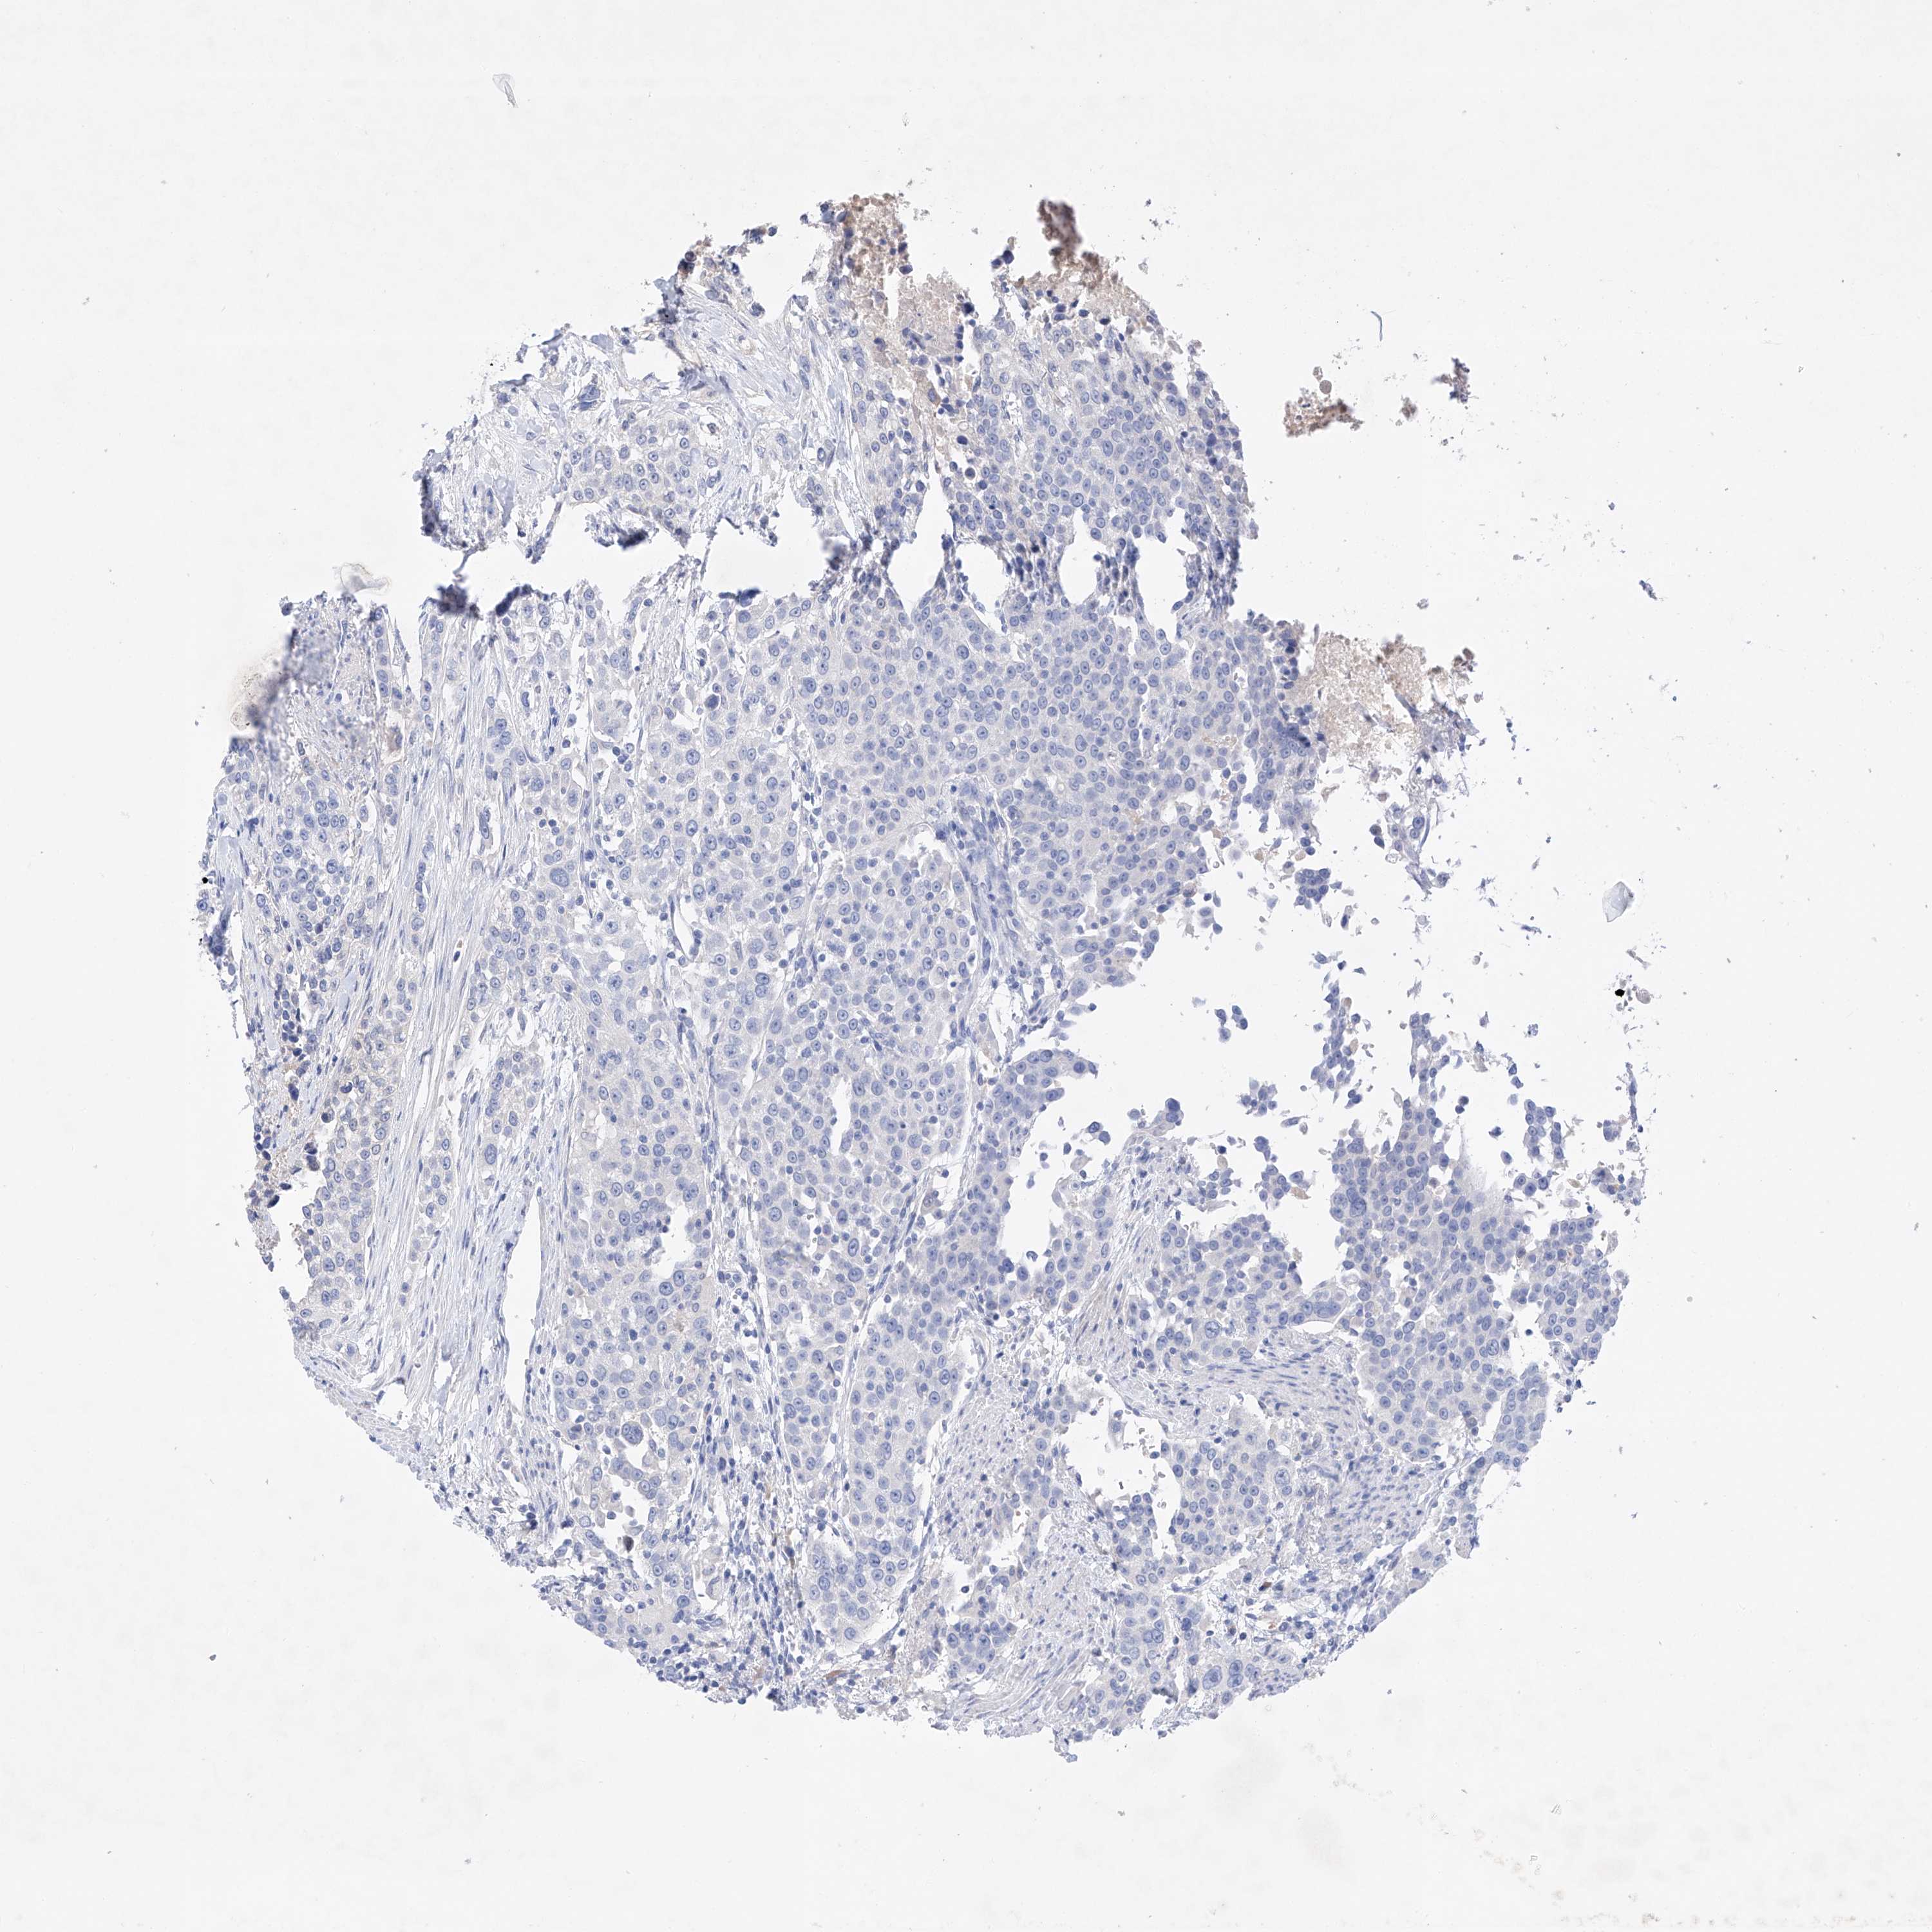

UROTHELIAL CANCER - Protein expressioni

A mouse-over function shows sample information and annotation data. Click on an image to view it in a full screen mode. Samples can be filtered based on level of antibody staining by selecting one or several of the following categories: high, medium, low and not detected. The assay and annotation is described here.

Note that samples used for immunohistochemistry by the Human Protein Atlas do not correspond to samples in the TCGA dataset.

Antibody stainingi

Antibody staining in the annotated cell types in the current human tissue is reported as not detected, low, medium, or high, based on conventional immunohistochemistry profiling in selected tissues. This score is based on the combination of the staining intensity and fraction of stained cells.

Each image is clickable and will lead to virtual microscopy that enables deeper exploration of all samples and also displays staining intensity scores, fraction scores and subcellular localization as well as patient and tissue information for each sample.

Antibody HPA030060

Antibody HPA030061

Urothelial carcinoma, Low grade

Urothelial carcinoma, High grade